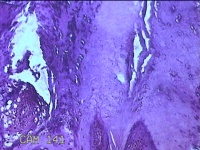

右侧拇指皮下结节

性别

男

年龄

40岁

临床诊断

皮下结节

一般病史

发现右侧拇指皮下结节1年余,无明显疼痛及不适。

标本名称

大体所见

灰白暗红色带皮肤结节0.8x0.3x0.2cm一个,表面糜烂,切开结节呈实性,切面灰白粉红色,质中。

图2